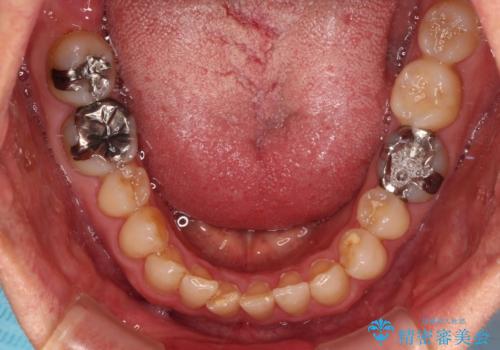

【モニター】ディープバイトで隙間の空いた歯列 ワイヤー装置での非抜歯矯正

- 前歯のデコボコと隙間の空いた歯列を気にして来院された患者様です。

下顎前歯が隠れるほどのディープバイトにより、強い咬合力と突き上げで上顎歯列に隙間が空いている状態でした。

手前に傾斜している奥歯をワイヤー装置で立ち上がらせ、咬み合わせの高さを挙上することで突き上げを解消し、空隙歯列を改善していくこととしました。